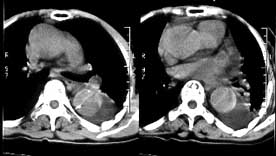

女性,71岁,胸骨后疼痛两小时来诊。体检:心界左下扩大,心率70次/每分,律齐,无杂音。x线胸片示:纵隔增宽。

ct平扫:降主动脉全程约18cm范围内管腔扩张,管腔被条索影分隔成前内、外后两腔,条索影与管壁连接处见散在点状钙化影。

增强扫描:见前内腔较小,与主动脉弓同步强化;后外腔较大,造影剂消退时间教主动脉弓延长,切管壁不均匀增厚,强化不明显。

ct诊断:降主动脉夹层动脉瘤,伴附壁血栓形成。